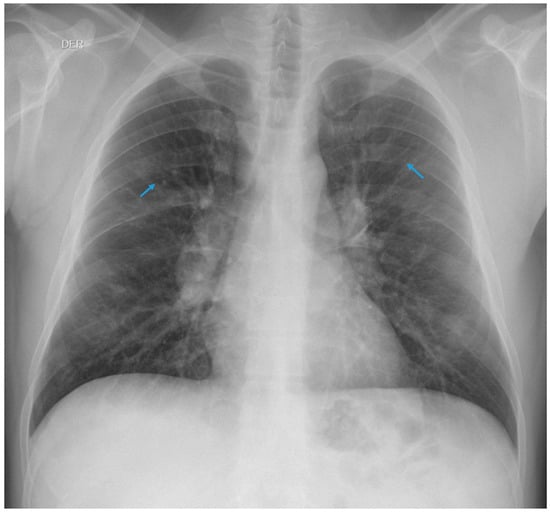

3.1.1. Case 1

3.1.2. Case 2